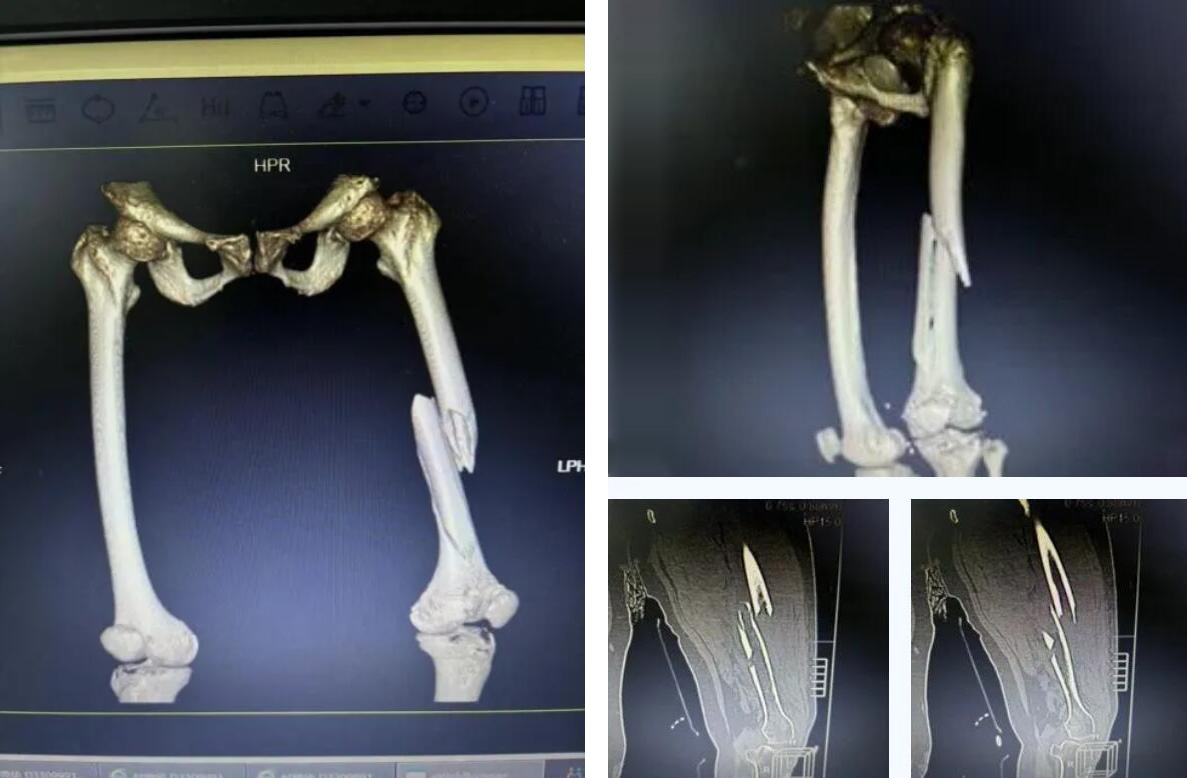

術(shù)前患者骨折CT影像

股骨,即人體的大腿骨,是全身最長(zhǎng)的骨骼,對(duì)于高齡老人,尤其是超過(guò)90歲的超高齡老人而言,髖部骨折常被稱(chēng)為“人生最后一次骨折”,死亡率極高。

而俞奶奶的股骨中段的多段骨折,手術(shù)難度和風(fēng)險(xiǎn)更是呈幾何級(jí)數(shù)增加,傳統(tǒng)的開(kāi)放手術(shù)創(chuàng)傷大、出血多,老人脆弱的心肺功能難以承受。